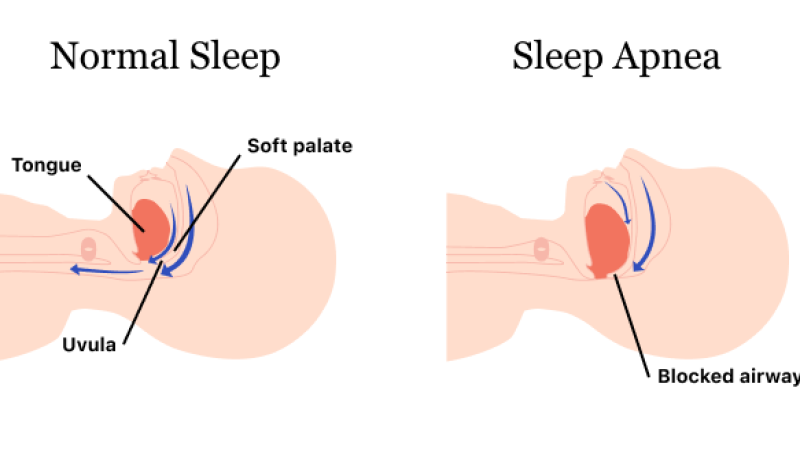

وقفه خواب

درمان وقفه تنفسی در خواب، بستری مجدد برای مشکلاتِ قلبی در افراد میانسال و سالمند را کاهش میدهد.

حدود 60% از کسانی که بیماری قلبی- عروقی دارند، از وقفهی تنفسی در خواب نیز رنج...